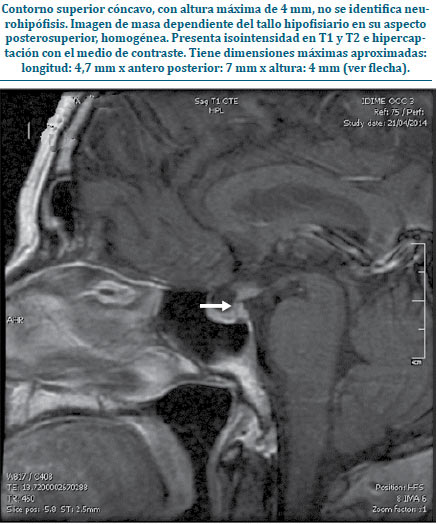

Al servicio de endocrinología, ingresa paciente de género masculino de 38 años, procedente de Puerto López (Meta, Colombia) con antecedente de infertilidad, disminución de la libido, y de las eyaculaciones, asociado a disfunción sexual. Al examen físico se evidenció hipogonadismo, signos de resistencia a la insulina y síntomas de hipotiroidismo (aumento de peso, astenia, adinamia, sensibilidad al frío). El paciente trae reporte de espermograma con hallazgos de azoospermia e hipospermia, paraclínicos que evidencian supresión de todos los ejes hipofisiarios sin hiperprolactinemia (tabla 1) y RMN de silla turca donde llama la atención ausencia de neurohipófisis y diagnóstico presuntivo de pituicitoma (figura 1).

| Figura 1. RMN de silla turca contrastada |

A pesar de que no existen hallazgos radiológicos patognomónicos de esta lesión, la tomografía axial computarizada (TAC) y la resonancia magnética nuclear (RMN) ayudan a hacer una aproximación diagnóstica. En la TAC se puede encontrar una lesión sólida bien circunscrita, mientras que en la RMN se puede evidenciar una lesión isointensa en T1 e hiperintensa en T2(6,11), estos últimos compatibles con los hallazgos en nuestro caso número 1.